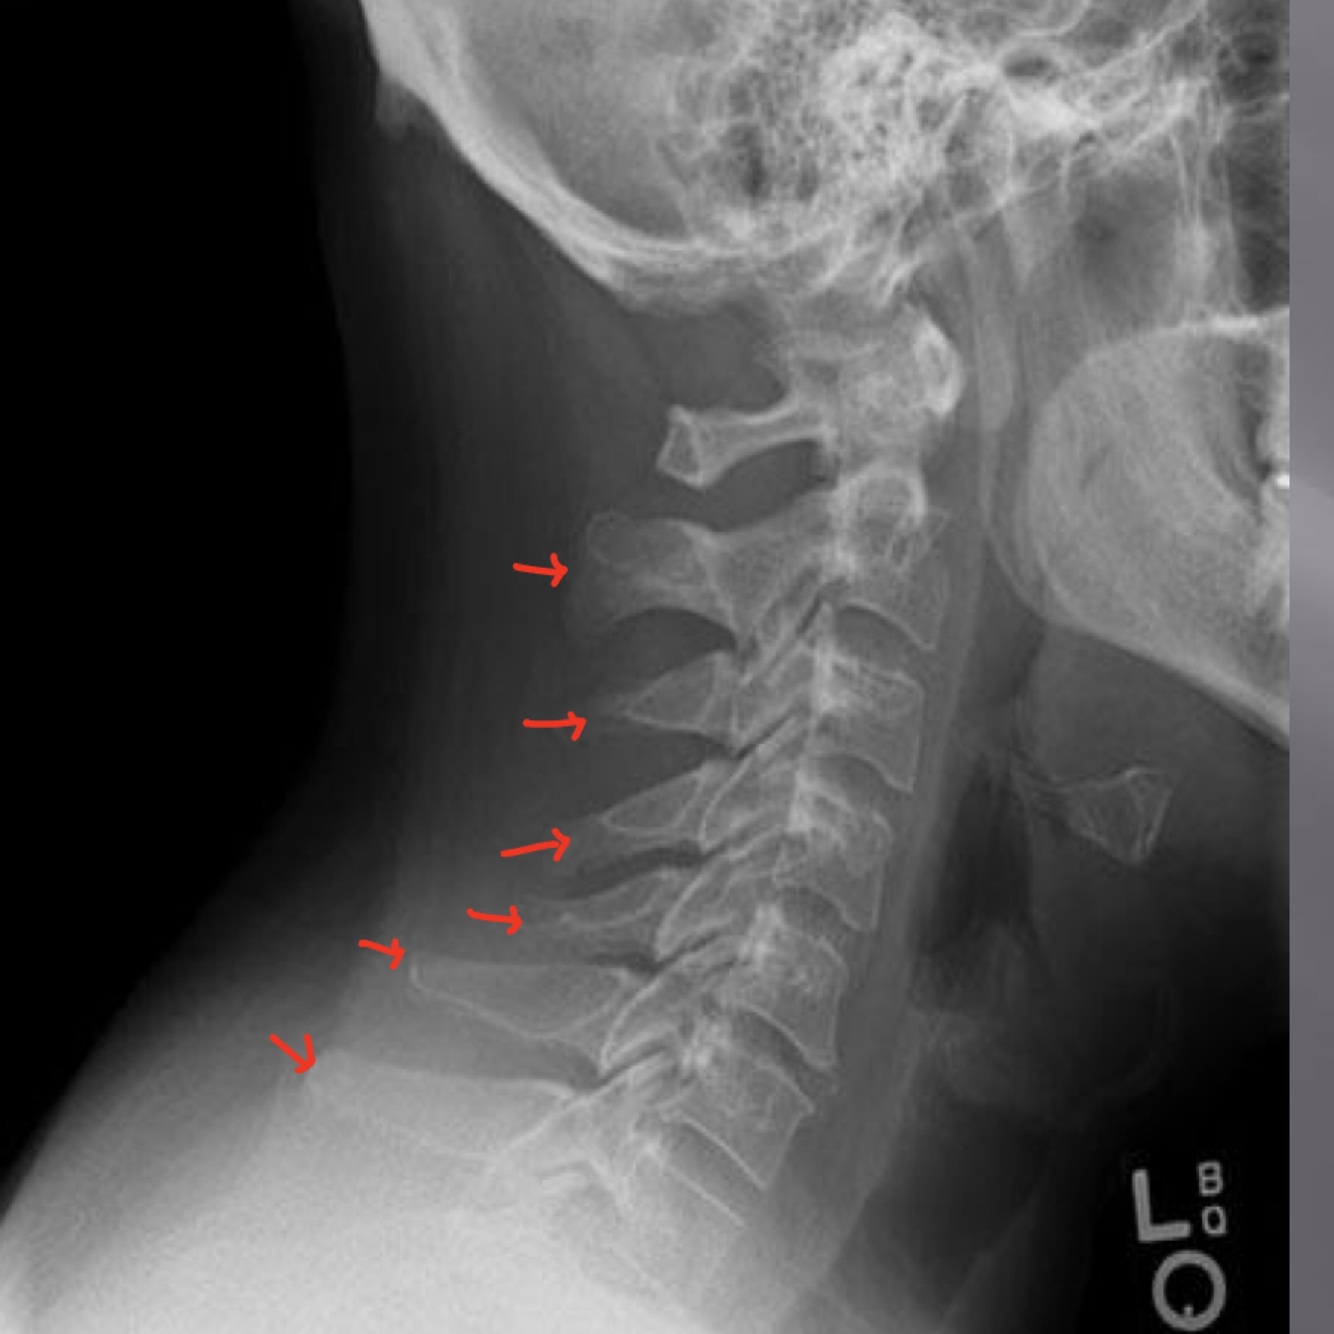

LATERAL CERVICAL LANDMARKS lateral cervical view

external acoustic meatus

mastoid process (air cells)

posterior tubercle of c1

angle of mandible

EOP

spinous process C2-C7

dens

posterior arch of C1

lamina c2-c7

vertebral body c2-c7

rami of mandible

body of mandible

transverse process of c2-c7

anterior tubercle c1

zygapophyseal joints

petrous portion

occipital condyle

superior endplate tips

inferior endplate tips

Lateral cervical view

disc spaces

atlanto-dental interspace

hyoid bone